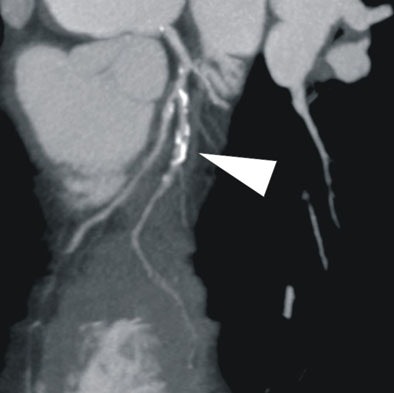

| In a 64-year-old man with chest pain, image of the corresponding slice shows inferior ischemia (arrows). |